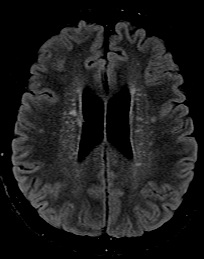

Results: A 38-year-old male developed tremors affecting the head and bilateral upper extremities two weeks after initiating escitalopram for anxiety. Head tremor had oscillations in vertical and horizontal planes. Upper extremities had Holmes tremor[4]–[6], 3–5 Hz in frequency, low-amplitude, seen at rest and action. Tremors persisted despite discontinuation of escitalopram. Magnetic Resonance Imaging showed extensive patchy, confluent T2 FLAIR signal abnormality involving bilateral basal ganglia, midbrain, and bilateral medial temporal lobes with punctate foci extending superiorly into the corona radiata, without gadolinium enhancement. This was stable on serial imaging. Cerebrospinal fluid (CSF) analysis showed oligoclonal bands and lymphocytic pleocytosis. Infectious, autoimmune, and paraneoplastic panels (serum and CSF) were negative except for minimally elevated Glutamic Acid Decarboxylase (GAD-65) antibodies in serum only. A PET scan identified increased uptake in left thyroid lobe, and histopathology from thyroidectomy confirmed papillary thyroid carcinoma. With imaging and serological workup suggesting paraneoplastic/autoimmune rhombencephalitis, immunotherapy with pulse steroids and plasma exchange was initiated without significant benefit. Intravenous immunoglobulin and cyclophosphamide provided limited neurological improvement. Tremors were refractory to multiple medication trials: head tremor responded to botulinum toxin injections, and trihexyphenidyl modestly improved upper extremity tremors. Over the next two years, he developed pseudobulbar affect and progressive gait instability, leading to walker-dependence.

T2/FLAIR Hyperintensities Bilateral Corona radiata